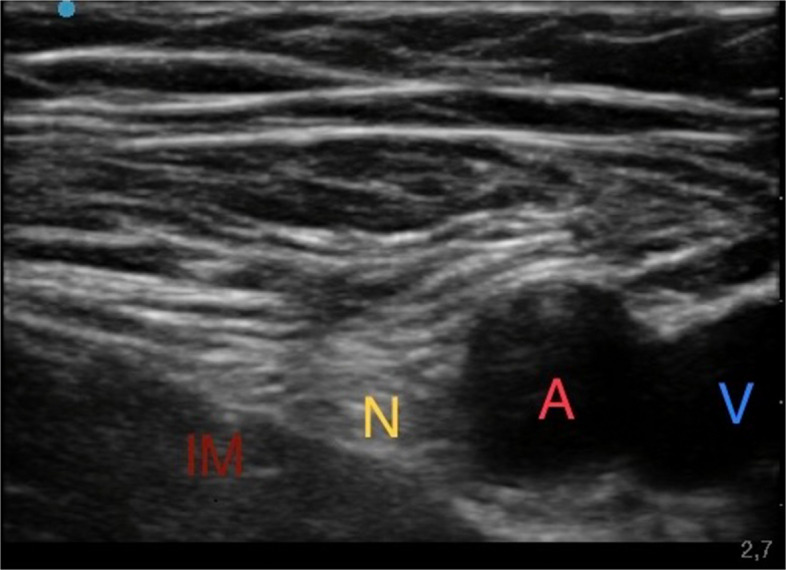

Ultrasound Femoral Nerve Block

First, the patient was positioned in supine decubitus with the lower limbs slightly abducted. With the aid of a linear ultrasound probe (Sonosite HLF38 × 13–6 MHz, Fujifilm Sonosite Europe, Amsterdam, The Netherlands), the inguinal ligament was located, which presents as a hyperechoic structure; the femoral vein, which is compressible, and the femoral artery, which is noncompressible and pulsatile, were located. More laterally the femoral nerve was identified as a hyperechoic triangle. From the lateral side of the transducer, an 80-mm-long, 21-gauge 30° tip (Pajunk) was inserted to ensure optimal visualization of the needle tip. The needle was directed under continuous ultrasound guidance below the iliac fascia near the lateral aspect of the femoral nerve, and then an anesthetic solution of Ropivacaine 0.375% (dose 26.25 mg) plus Mepivacaine 1% (dose 70 mg) and Dexamethasone 4 mg (total volume 15 ml) were subsequently injected until complete detachment of the iliac fascia (Fig. 1).

Fig. 1.

Ultrasound femoral nerve block. Iliac muscle (IM); Femoral nerve (N); Femoral artery (A); Femoral vein (V)